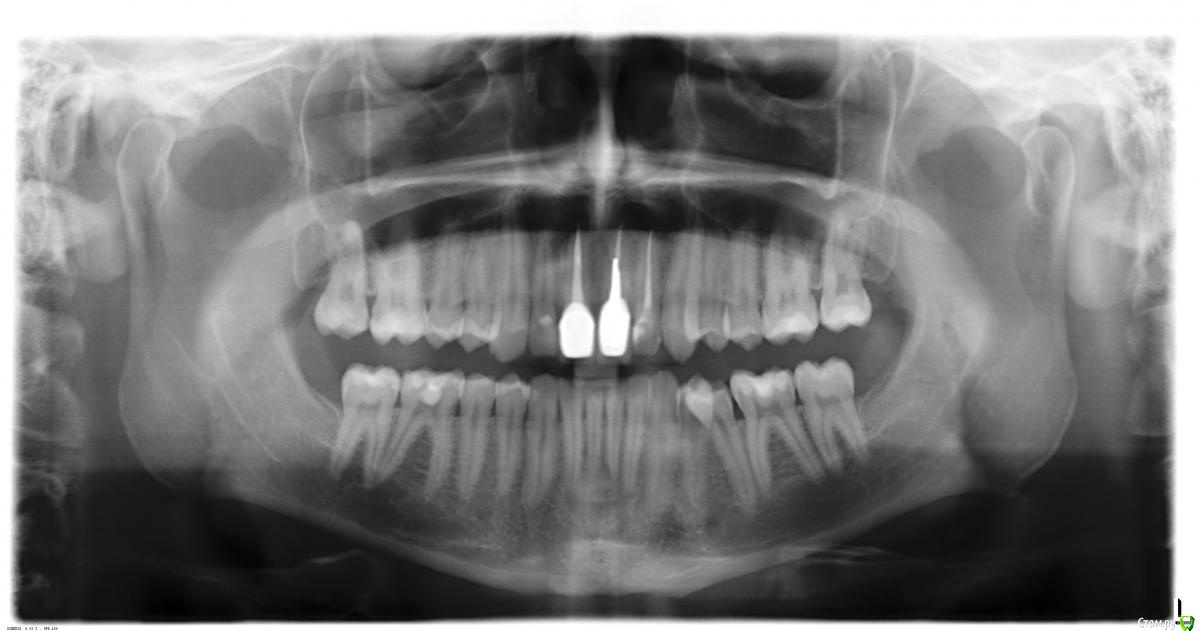

Доброй ночи, такая ситуация, 3 года назад поставили коронку единичка, 9 июля начала болеть десна там где эта коронка, сказали воспалился сосочек десны, полоскал и мазал специальной пастой 20 июля перестало болеть, 4 сентября опять начало болеть причем намного сильнее, пошел к стоматологу он сказал не страшно прописал нимисин и пасту, боль стала невыносимой и заметил, что коронка опустилось чу чуть, пошел к другому стоматологу сделали снимок и стучал по зубам больно очень было 2-ке, сказал пульпит на ней и удалил пульпу, про коронку сказал, что не поменять коронка так и будет, но проблема в том, что жевать не могу нажимаю на коронку и десне больно и она ходит чу чуть, можно ли ее снять и заного одеть?

Снимки фото прилагаю.